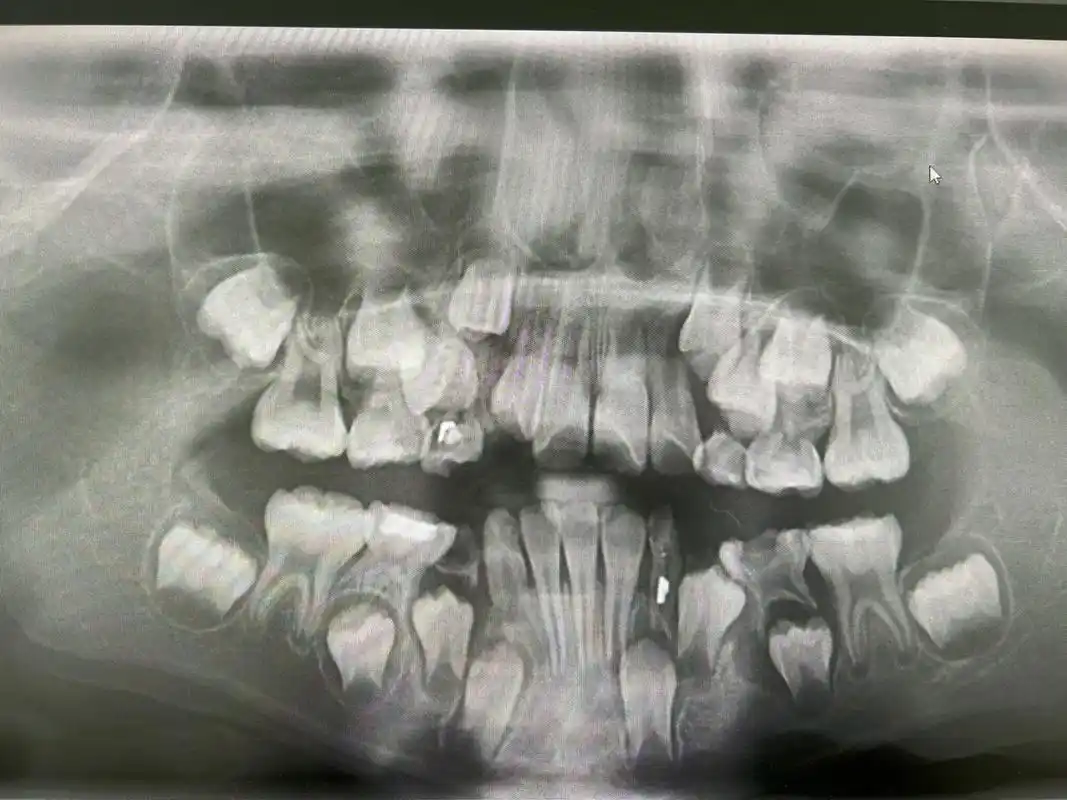

换牙期小朋友的牙片可以清楚看到有四排牙齿 (还有两颗是长在眼睛下方

快来看看小孩子换牙期的牙片#牙片分析 #满脸都是牙 - 抖音

无意看到一个小朋友的全景牙片看完毛骨悚然这是正常的吗

替牙期儿童拍摄全景牙片的意义这个孩子发现有多生牙和牙胚缺失